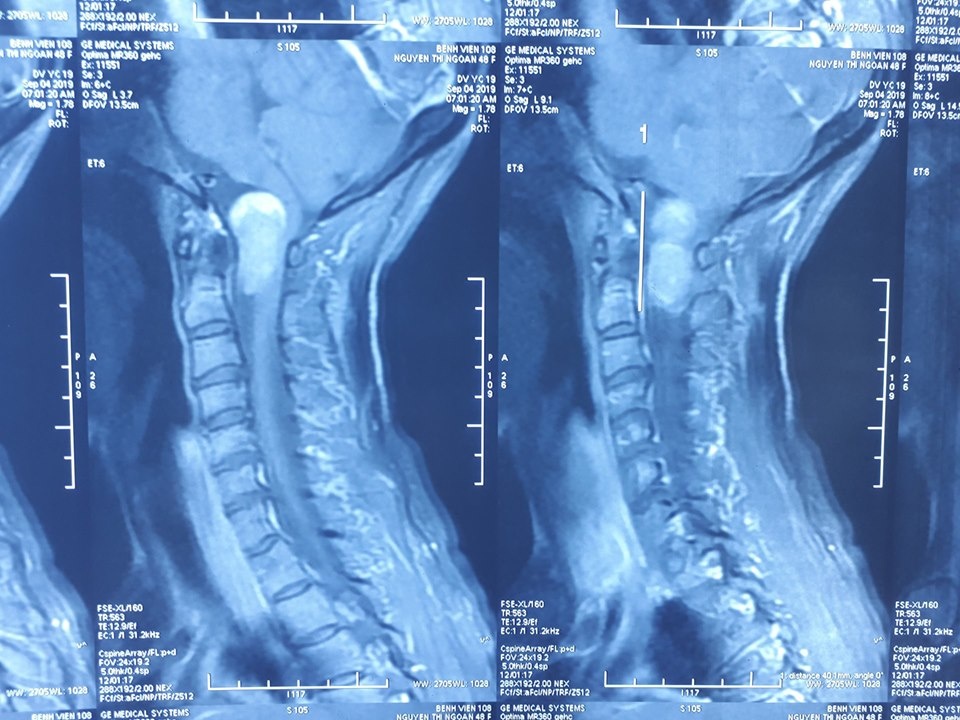

| Hình ảnh khối u của nữ bệnh nhân. Ảnh: BVCC. |

Sau khi được làm các xét nghiệm, chụp X-quang, các bác sĩ chẩn đoán bệnh nhân bị u rễ thần kinh vùng chẩm cổ, khối u chèn ép tủy sống và hành tủy.

Trong quá trình phẫu thuật, sau khi phẫu tích dưới kính hiển vi, các bác sĩ bất ngờ phát hiện khối u xuất phát từ rễ thần kinh cổ 2 đã phát triển ống sống lan tỏa lên sọ não. Các bác sĩ phải rất khéo léo trong quá trình phẫu thuật, bởi dễ dẫn đến nguy cơ suy hô hấp. Sau ca mổ kéo dài hơn 2 giờ, các bác sĩ đã lấy khối u vùng chẩm cổ kích thước 3x2 cm ra khỏi bệnh nhân.